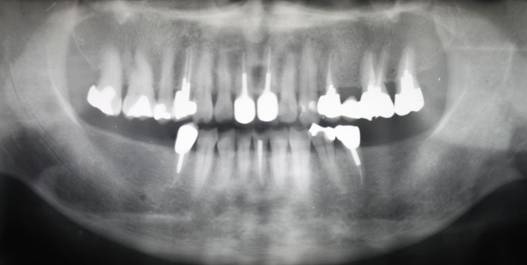

術前パノラマレントゲン写真。根の周りが黒くなり、骨がなくなっていることがわかります

治療後。歯周病で失われた骨が回復しています。使用インプラントはスプラインツイストです。

術前のパノラマレントゲン写真。仮歯を支えている4本の歯は根が残っているだけで抜歯の必要がありました。

63歳術後のパノラマレントゲン。インプラントはスプラインツイスト